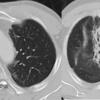

Radiation Case 5 seq

Date: 02/27/2009

Views: 30640